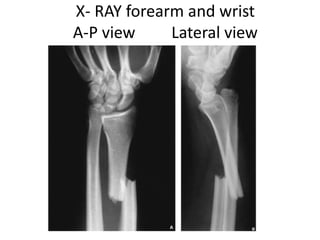

X- RAY forearm and wrist

A-P view Lateral view

Plain Radiographs • radialshaft fracture – commonly at the junction of the middle and distal third – dorsal or volar angulation • dislocation of the distal radioulnar joint • radial shortening may occur

• 19.

X- RAY forearmand wrist A-P view Lateral view

• #19 radial shortening may occur, and if greater than 10 mm, suggests complete disruption of the interosseous membrane A forearm series is usually sufficient for diagnosis and management planning. However, good quality orthogonal views are needed to identify and characterise displacement correctly.